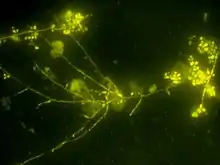

Candida albicans (responsable du « muguet blanc »), l'espèce la plus fréquente, fait partie de la flore habituelle de l'oropharynx ou du tube digestif, et peut aussi être présent en faible quantité dans la flore vaginale normale.

Candidose pseudo-membraneuse (muguet)

C'est la forme la plus courante, elle commence par un érythème de la langue puis apparaissent des lésions blanches et jaunâtres inflammatoires et confluentes. Viennent couramment s'ajouter aux signes précédents une xérostomie et une sensation de cuisson de la bouche. Il arrive parfois que cette forme soit purement érythémateuse.